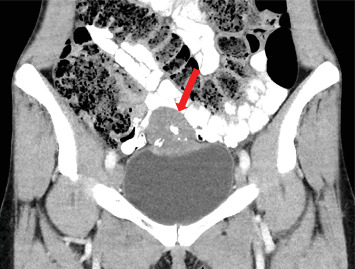

原发性膀胱印戒细胞癌(PSRCCB)是一种极为罕见的膀胱癌亚型,约占病例的0.12%-0.6%,预后较差。本病例报告详细介绍了一个独特的32岁女性PSRCCB病例,没有典型的危险因素,提出了诊断和治疗的挑战。最初症状包括尿路感染和下腹部疼痛。影像学和组织学评估确定了一种带有印戒细胞成分的粘液腺癌。考虑到患者年龄小,肿瘤局限,由于肿瘤切除完全,无转移,避免了淋巴结切除和辅助化疗,行了根治性开放性部分膀胱切除术。术后随访未见病理发现,强调了个体化治疗策略在罕见癌症病例中的重要性。本病例对PSRCCB及其管理的有限数据有所贡献。

Primary signet ring cell carcinoma of the urinary bladder (PSRCCB) is an exceedingly rare subtype of urinary bladder carcinoma, comprising 0.12%-0.6% of cases, with a poor prognosis. This case report details a distinctive case of a 32-year-old woman with PSRCCB, presenting without typical risk factors and posing diagnostic and therapeutic challenges. Initial symptoms included urinary tract infection and lower abdominal pain. Imaging and histological assessments identified a mucinous adenocarcinoma with signet ring cell components. The patient underwent curative open partial cystectomy, given her young age and localized tumor, avoiding lymphadenectomy and adjuvant chemotherapy due to complete tumor resection and absence of metastases. Postoperative follow-up showed no pathological findings, underscoring the importance of individualized treatment strategies in rare cancer cases. This case contributes to the limited data on PSRCCB and its management.